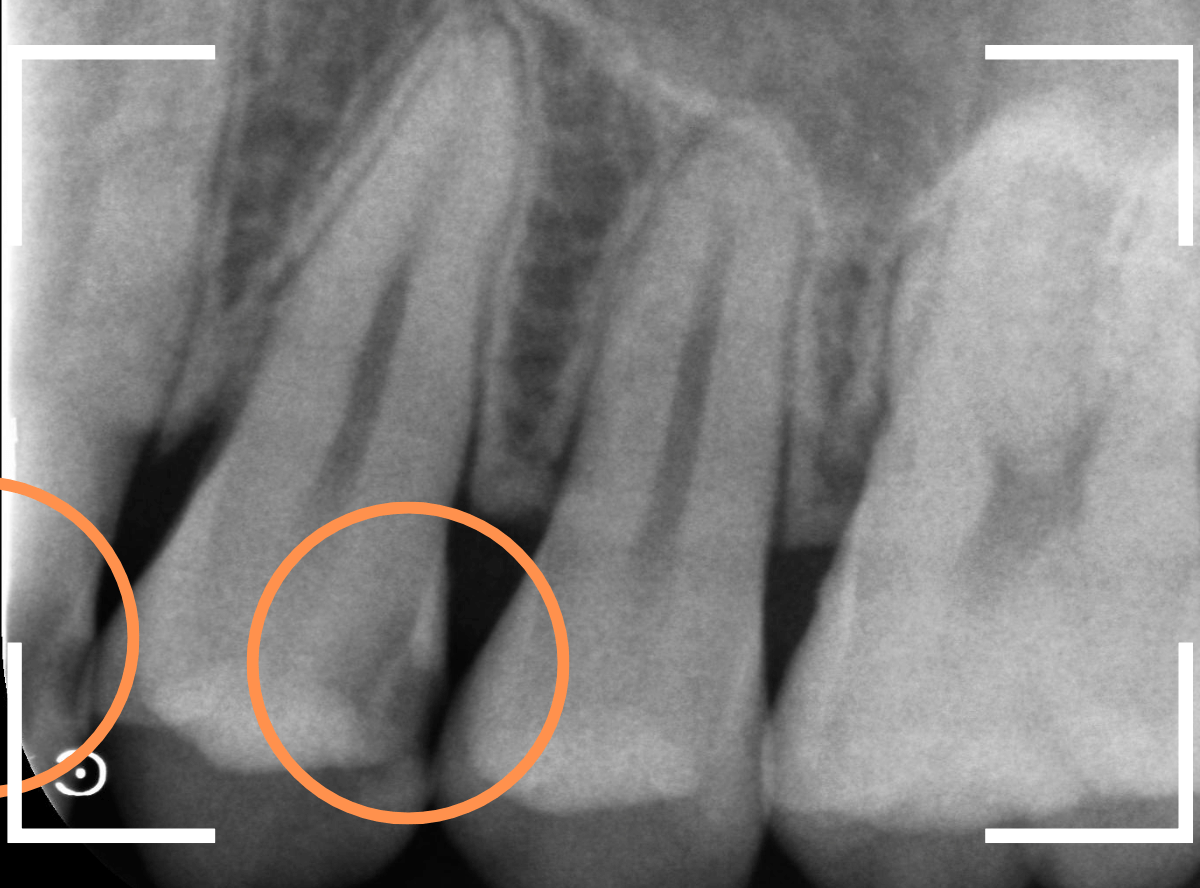

Case.26 <動画編> 症状もなく、深く進行する「歯と歯の間の虫歯治療」

今回は、歯と歯の間で大きな虫歯が進行しているケースです。

見た目に虫歯は見当たらず、痛みもありませんが、レントゲン写真で確認すると、歯と歯の間から、歯の神経まで達するほど虫歯が広がっています。

これほど大きな虫歯でも、症状がない事は多くあります。

Case.22 痛みはないけど、歯のすきまから大きな虫歯

上の小臼歯の間が虫歯になっていた患者さんです。

症状はありませんし、見た目からも虫歯があるかはわかりませんでした。

レントゲン写真で確認します。

赤い線が虫歯、青い線が歯の神経です。

歯のすきまから両側に虫歯が大きく広がっているのが確認できます。